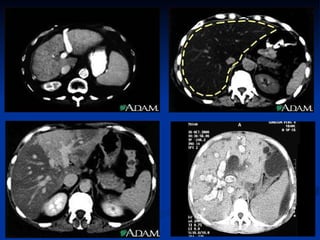

Imaging  Ultrasound   ,  CT and MRI are  routinely used in the evaluation of cirrhosis, where it may show a small and nodular liver in advanced cirrhosis along with increased echogenicity with irregular appearing areas. Ultrasound may also screen for hepatocellular carcinoma, portal hypertension and Budd-Chiari syndrome (by assessing flow in the hepatic vein).

Computed tomography scans (CT), ultrasound, and other imaging techniques can be used during diagnosis. They can help determine the size of the liver, indicate healthy and scarred areas of the organ, and detect gallstones. Cirrhosis is sometimes diagnosed during surgery or by examining the liver with a laparoscope. This viewing device is inserted into the patient's body through a tiny incision in the abdomen.